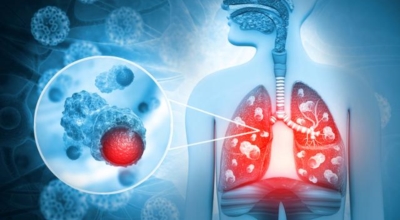

폐에 발생된 악성 종양을 말하며 오랜 기간 흡연해온 남성들에서 발병률이 높고 요즈음 각종 환경적인 요인의 영향과 간접흡연으로 흡연하지 않는 여성에서도 많이 발생하고 있습니다. 증상을 느껴 병원을 찾았을 때는 수술하기 늦은 경우가 많아 사망 가능성이 매우 높은 암입니다. 폐 자체에서 발생하거나 다른 장기에서 발생된 암이 폐로 전이되어 발생하기도 하고 특별한 초기 증상이 없는 경우가 많고 암이 진행된 후에도 공통적인 감기 증상인 기침과 가래 외의 특이 증상이 나타나지않아 증상만으로는 진단이 쉽지 않습니다.

간접흡연 외에도 공사장과 같은 곳에서 미세먼지나 석면, 비소, 라돈, 카드뮴 등 육체에 나쁜 성분에 노출되는 환경적 요인으로 폐암이 발병할 수 있으며 유전적 요인으로도 폐암이 발병할 수 있다고 하죠. 가족 중 폐암을 앓았던 분들이 있다면 그렇지 않은 분들에 대조해 2배 가량 더 폐암에 걸릴 확률이 높다고 하는데요 이렇듯 폐암은 나도 모르는 새에 발병할 수 있기 때문에 자신의 체력 상태를 자주 체크하여 폐암을 초기에 발견하는 것이 현명합니다.

폐암 검사는 X-ray를 통해서 검사하는데 , 크기가 작거나 구석에 위치한 경우 확인이 어려운 경우도 있답니다. 그리고 조직 검사를 통해서 정확한 진단을 하게 되어요. 폐암이 발견되면 종양의 크기나 전이 여부 , 위치에 따라서 수술 여부를 결정하게 됩니다.